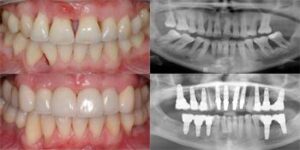

Teeth are held strongly in the jaw by alveolar bone. Gum infection will lead to destruction of the bone holding the tooth. In most of the cases it happens very slowly and patients are not aware of it.

Usually on a routine dental visit the dentist will identify the gum infection substantiated by X-ray investigation.

Normal periodontal treatments and elimination of the underlying cause can get the disease under control. There are conditions which are refractory or not responding to the routine treatment which will continue to an extent where the teeth are very loose and beyond saving the teeth. In such situations the treatment of choice is to replace the loose teeth with dental implants.